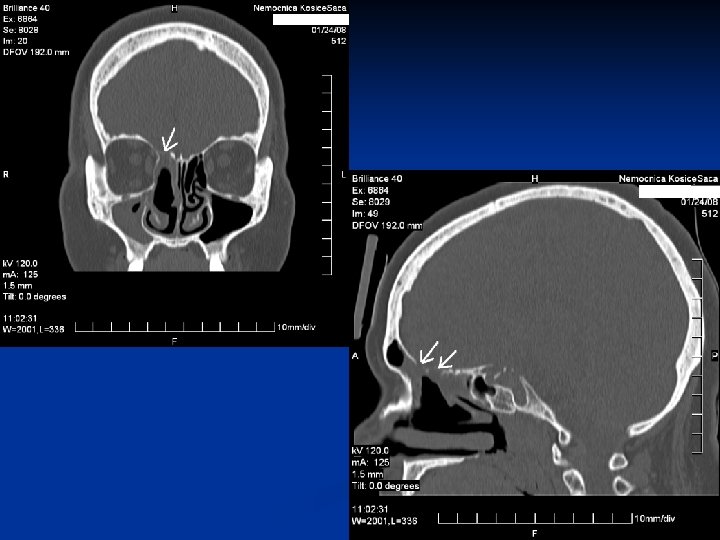

Kazuistika č. 1 n n n 67 ročná pacientka Infekt HCD v 02/2015, odvtedy výtok čírej tekutiny z pr. nosnej dierky, bolesť hlavy 29. 7. 2015 prvé vyš. na našej ORL amb. Vyš. β 2 TRF – potvrdenie likvoru CT PND Suponovaná idiopatická rinolikvorea vpravo, indik. FESS operácia na 21. 9. 2015

Kazuistika 2. n n n 48 ročný pacient Obojstranná FESS operácia v CA pre nosovú polypózu Predoperačne lokálne a celkovo kortikoidy 2. pooperačný deň udáva výtok čírej tekutiny z pravej nosovej dierky Na základe anamnézy, endoskopického vyš. a HRCT diagnostikovaná iatrogénne spôsobená rinolikvorea vpravo v oblasti lamela lateralis, indikovaná duraplastika vpravo

Kazuistika 3. n n n 61 - ročná pacientka FESS operácia vpravo pre nosovú polypózu s postihnutím pravej maxilárnej, čelovej dutiny a predných ethmoidov Peroperačne odstránený zo stredného nosového priechodu cystický polypózny útvar, dutiny vyplnené hlienohnisom Pacientka týždeň po operácii pri amb. kontrole udáva výtok čírej tekutiny z pravej nos. dierky Na základe anamnézy, endoskopického nálezu a HRCT diag. rinolikvorea v oblasti nazofrontálneho vývodu a stropu ethmoidov, indikovaná duraplastika vpravo Stav hodnotíme ako meningokélu s následnou rinolikvoreou